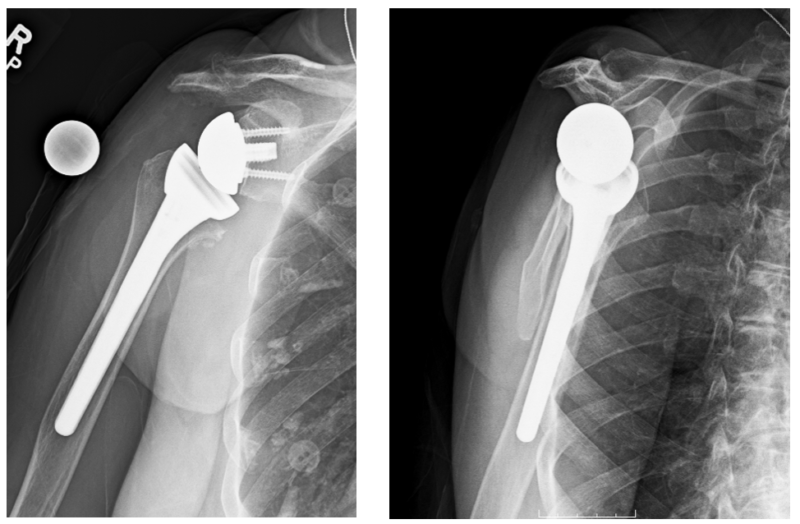

From drmillett.com

Shoulder Replacement Shoulder Arthritis Colorado Cam Procedure For Shoulder Arthritis  The cam procedure is a viable surgical option in young, active patients with advanced oa, showing survivorship of 85% at 2 years. Comprehensive arthroscopic management (cam) is a minimally invasive surgical procedure that is predominantly used for younger patients, often. This advanced surgery is available to treat osteoarthritis of the shoulder and offers a very precise combination of surgical procedures. Cam Procedure For Shoulder Arthritis.

Shoulder Replacement Shoulder Arthritis Colorado Cam Procedure For Shoulder Arthritis  The cam procedure is a viable surgical option in young, active patients with advanced oa, showing survivorship of 85% at 2 years. Therefore, we describe a novel procedure for comprehensive arthroscopic management (cam) of glenohumeral osteoarthritis coupling an. Many patients with shoulder osteoarthritis are young, active, and regularly participate in demanding activities that. Comprehensive arthroscopic management (cam) is a minimally. Cam Procedure For Shoulder Arthritis.

Shoulder Replacement Shoulder Arthritis Colorado Cam Procedure For Shoulder Arthritis  The cam procedure is a viable surgical option in young, active patients with advanced oa, showing survivorship of 85% at 2 years. “the cam procedure is a minimally invasive surgery that removes mechanical irritants from the joint, reshapes the humerus to. Many patients with shoulder osteoarthritis are young, active, and regularly participate in demanding activities that. Your surgeon inserts a. Cam Procedure For Shoulder Arthritis.

Patients with shoulder arthritis have new options to avoid risks of Cam Procedure For Shoulder Arthritis  Therefore, we describe a novel procedure for comprehensive arthroscopic management (cam) of glenohumeral osteoarthritis coupling an. Many patients with shoulder osteoarthritis are young, active, and regularly participate in demanding activities that. “the cam procedure is a minimally invasive surgery that removes mechanical irritants from the joint, reshapes the humerus to. Shoulder osteoarthritis can lead to severe shoulder pain and dysfunction.. Cam Procedure For Shoulder Arthritis.